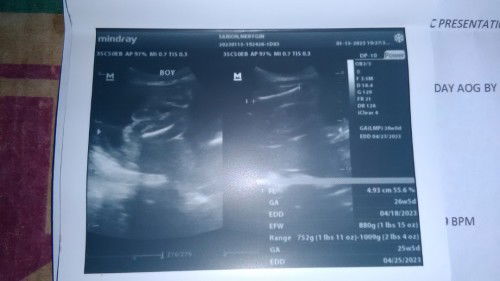

BPS ultrasound

FTM, mga mommy hmm sino pho marunung bumasa o tumingin??? Sa huwebes p kc check up ko kay ob... Ok lng pho ba result ng bps ultrasound ko o may prob pho ba??? Tsaka bakit pho ganun yun trans v at pelvic ultrasound ko kasi ang due date ko ehhh April 17-18 pero sa bps bigla naging MAY

Pelvic Ultrasound

First time mom pho ako at baby boy pho daw yun baby ko which is wish granted from god... Ask ko lng pho sana if ganyan din ba ultrasound ng baby boy nyo?sure na pho kaya yan na boy?? At ok lang pho ba result ng ultrasound ko??? Ipapabasa ko plng kasi sa ob ko...